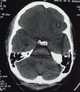

Venous cerebral infarction

Cerebral venous sinus thrombosis (CVST) is the presence of a blood clot in the dural venous sinuses, which drain blood from the brain. Symptoms may include headache, abnormal vision, any of the symptoms of stroke such as weakness of the face and limbs on one side of the body, and seizures. [Source: Wikipedia ]